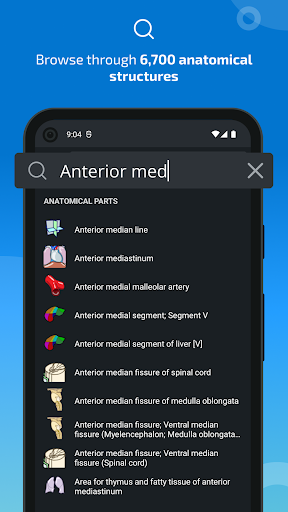

- Localice fácilmente las estructuras anatómicas gracias a la búsqueda de índice

*Encuentre sus partes anatómicas más fácilmente gracias a la nueva función de búsqueda, más intuitiva y poderosa.